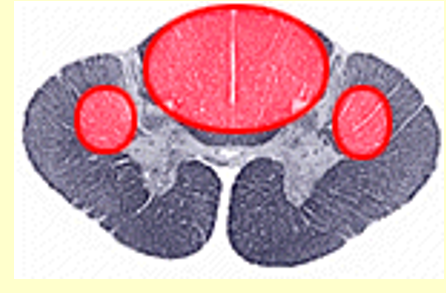

Dorsal column

spinothalamic

Anterior Spinal Syndrome

syringomyelia